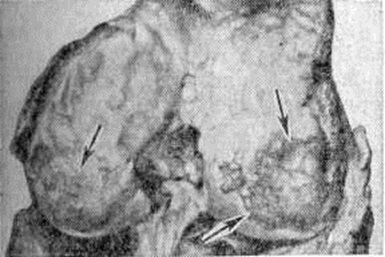

Патологическая анатомия процесса в динамике не изучена. Однако картины его исходов позволяют считать, что в основе болезни лежит механическая неполноценность хрящевого вещества, обусловленная отсутствием в организме субстанции, необходимой для формирования хряща, или, наоборот, поступлением в организм веществ, нарушающих этот процесс. На первый план выступают дистрофические изменения хряща мелких и крупных суставов конечностей, возрастающие соответственно степени болезни. Суставной хрящ мутнеет, истончается, иногда появляются узуры, проникающие в субхондральные отделы кости. Поверхности суставов неровные, шероховатые (рисунок 1). В наиболее нагружаемых участках хрящ стирается, отслаивается, обнажая кость (рисунок 2). Иногда суставная поверхность полностью лишается хрящевого покрытия и представляет собой отшлифованную кость. Суставные концы деформируются. В длинных костях образуются краевые костные разрастания, характерные для деформирующего артроза. В редких случаях наблюдается уплощение головок плечевых и бедренных костей (рисунок 3), которые могут принимать грибовидную форму, разрастание ворсин синовиальной оболочки с образованием рисовых тел. В полостях суставов могут быть свободные хрящевые и костные суставные тела. В грудном отделе позвоночника может развиваться кифоз, сколиоз, в поясничном — лордоз, обусловленный деформациями позвонков. Высота позвонков уменьшена вследствие остеопороза. В дисках появляются трещины, щели с гомогенным или крошковатым детритом. Со временем развиваются явления деформирующего спондилёза с характерными для него краевыми костными разрастаниями. Данных по микроскопическому исследованию костной системы не много, и относятся они лишь к исходам процесса у взрослых. В суставных хрящах обнаруживаются бесклеточные некротические участки, уменьшение базофилии межклеточного вещества, снижение содержания в нем кислых сульфатированных мукополисахаридов, что вызывает демаскирование хондриновых волокон, растрескивание и глыбчатый распад его.